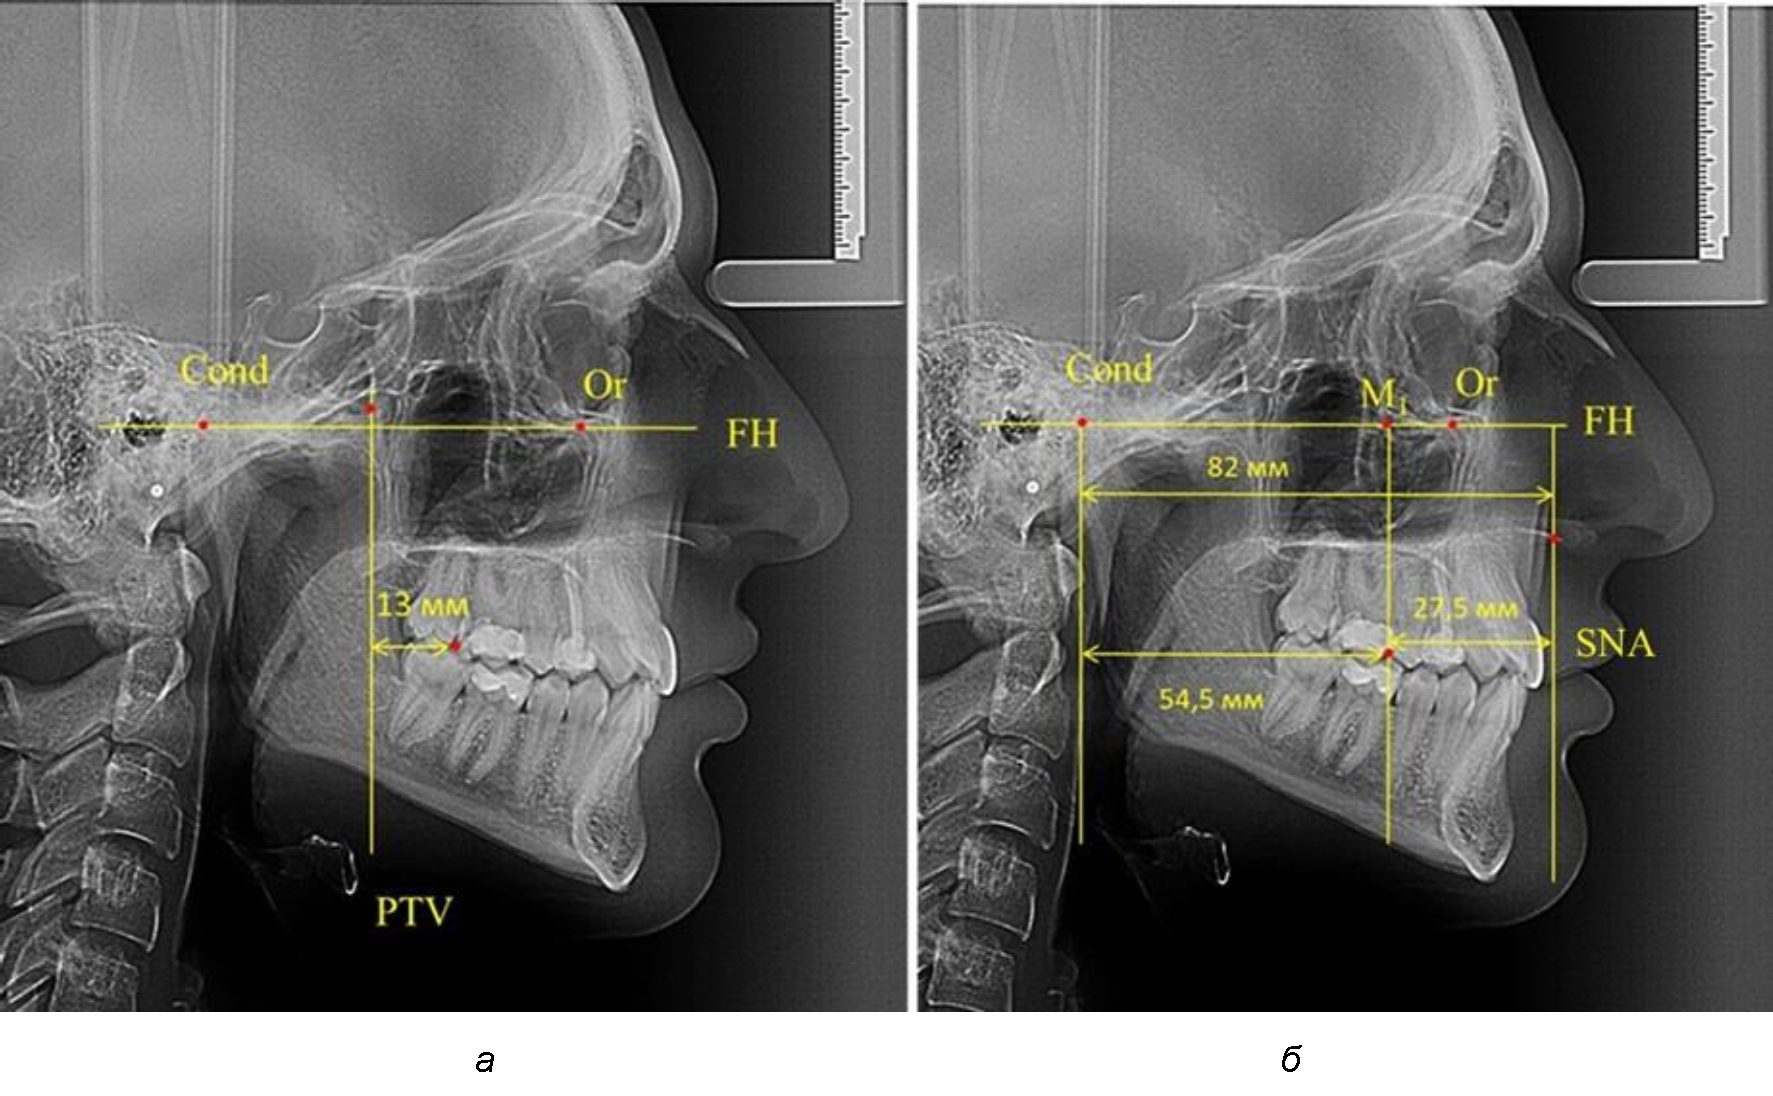

Рентгенограмма 16-летнего ребенка, с реперными линиями и анализируемыми линейными параметрами по двум используемым методам, представлена на рис. 6.

Рис. 6. Особенности положения первых моляров по R. E. McDonald (а) и по предложенному методу (б) у ребенка 16 лет

После прорезывания вторых постоянных моляров кондилярно-спинальный увеличивался до 80 мм.

Дистальная поверхность первого постоянного моляра отстояла от крыловидной вертикали на величину, составляющую около 18 мм, что, так же, как и в предыдущих периодах прикуса, было близким по значению к данным R. E. McDonald, а именно возраст, плюс 3 мм.

Обращает на себя внимание отношение глубины гнатического отдела лица к дистальному отделу, а именно к кондилярно-молярному расстоянию, которое, вне зависимости от сагиттальных размеров, составляло 1 : 1,5.